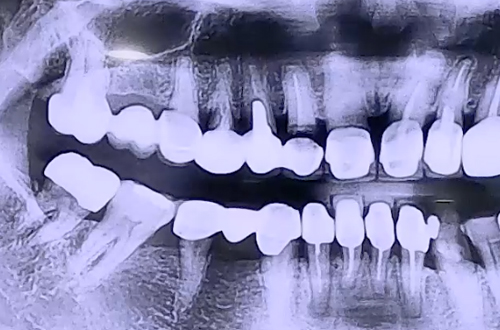

BEFORE

불편함을 느끼시는 치아를 살펴보니, 앞니부터 어금니까지

6개의 보철이 전부 붙어있는 형태를 하고 계셨던 환자분이십니다.

오른쪽 두번째 앞니 보철 안쪽으로 충치가 생기며 잇몸이 붓고 아프셨는데,

보철의 구조와 치료가 필요한 앞니의 상태가 발치를 한 뒤 임플란트를

진행해야 하는 상황이었기 때문에 앞니 보철을 절단하고 임플란트를 해 드렸습니다.